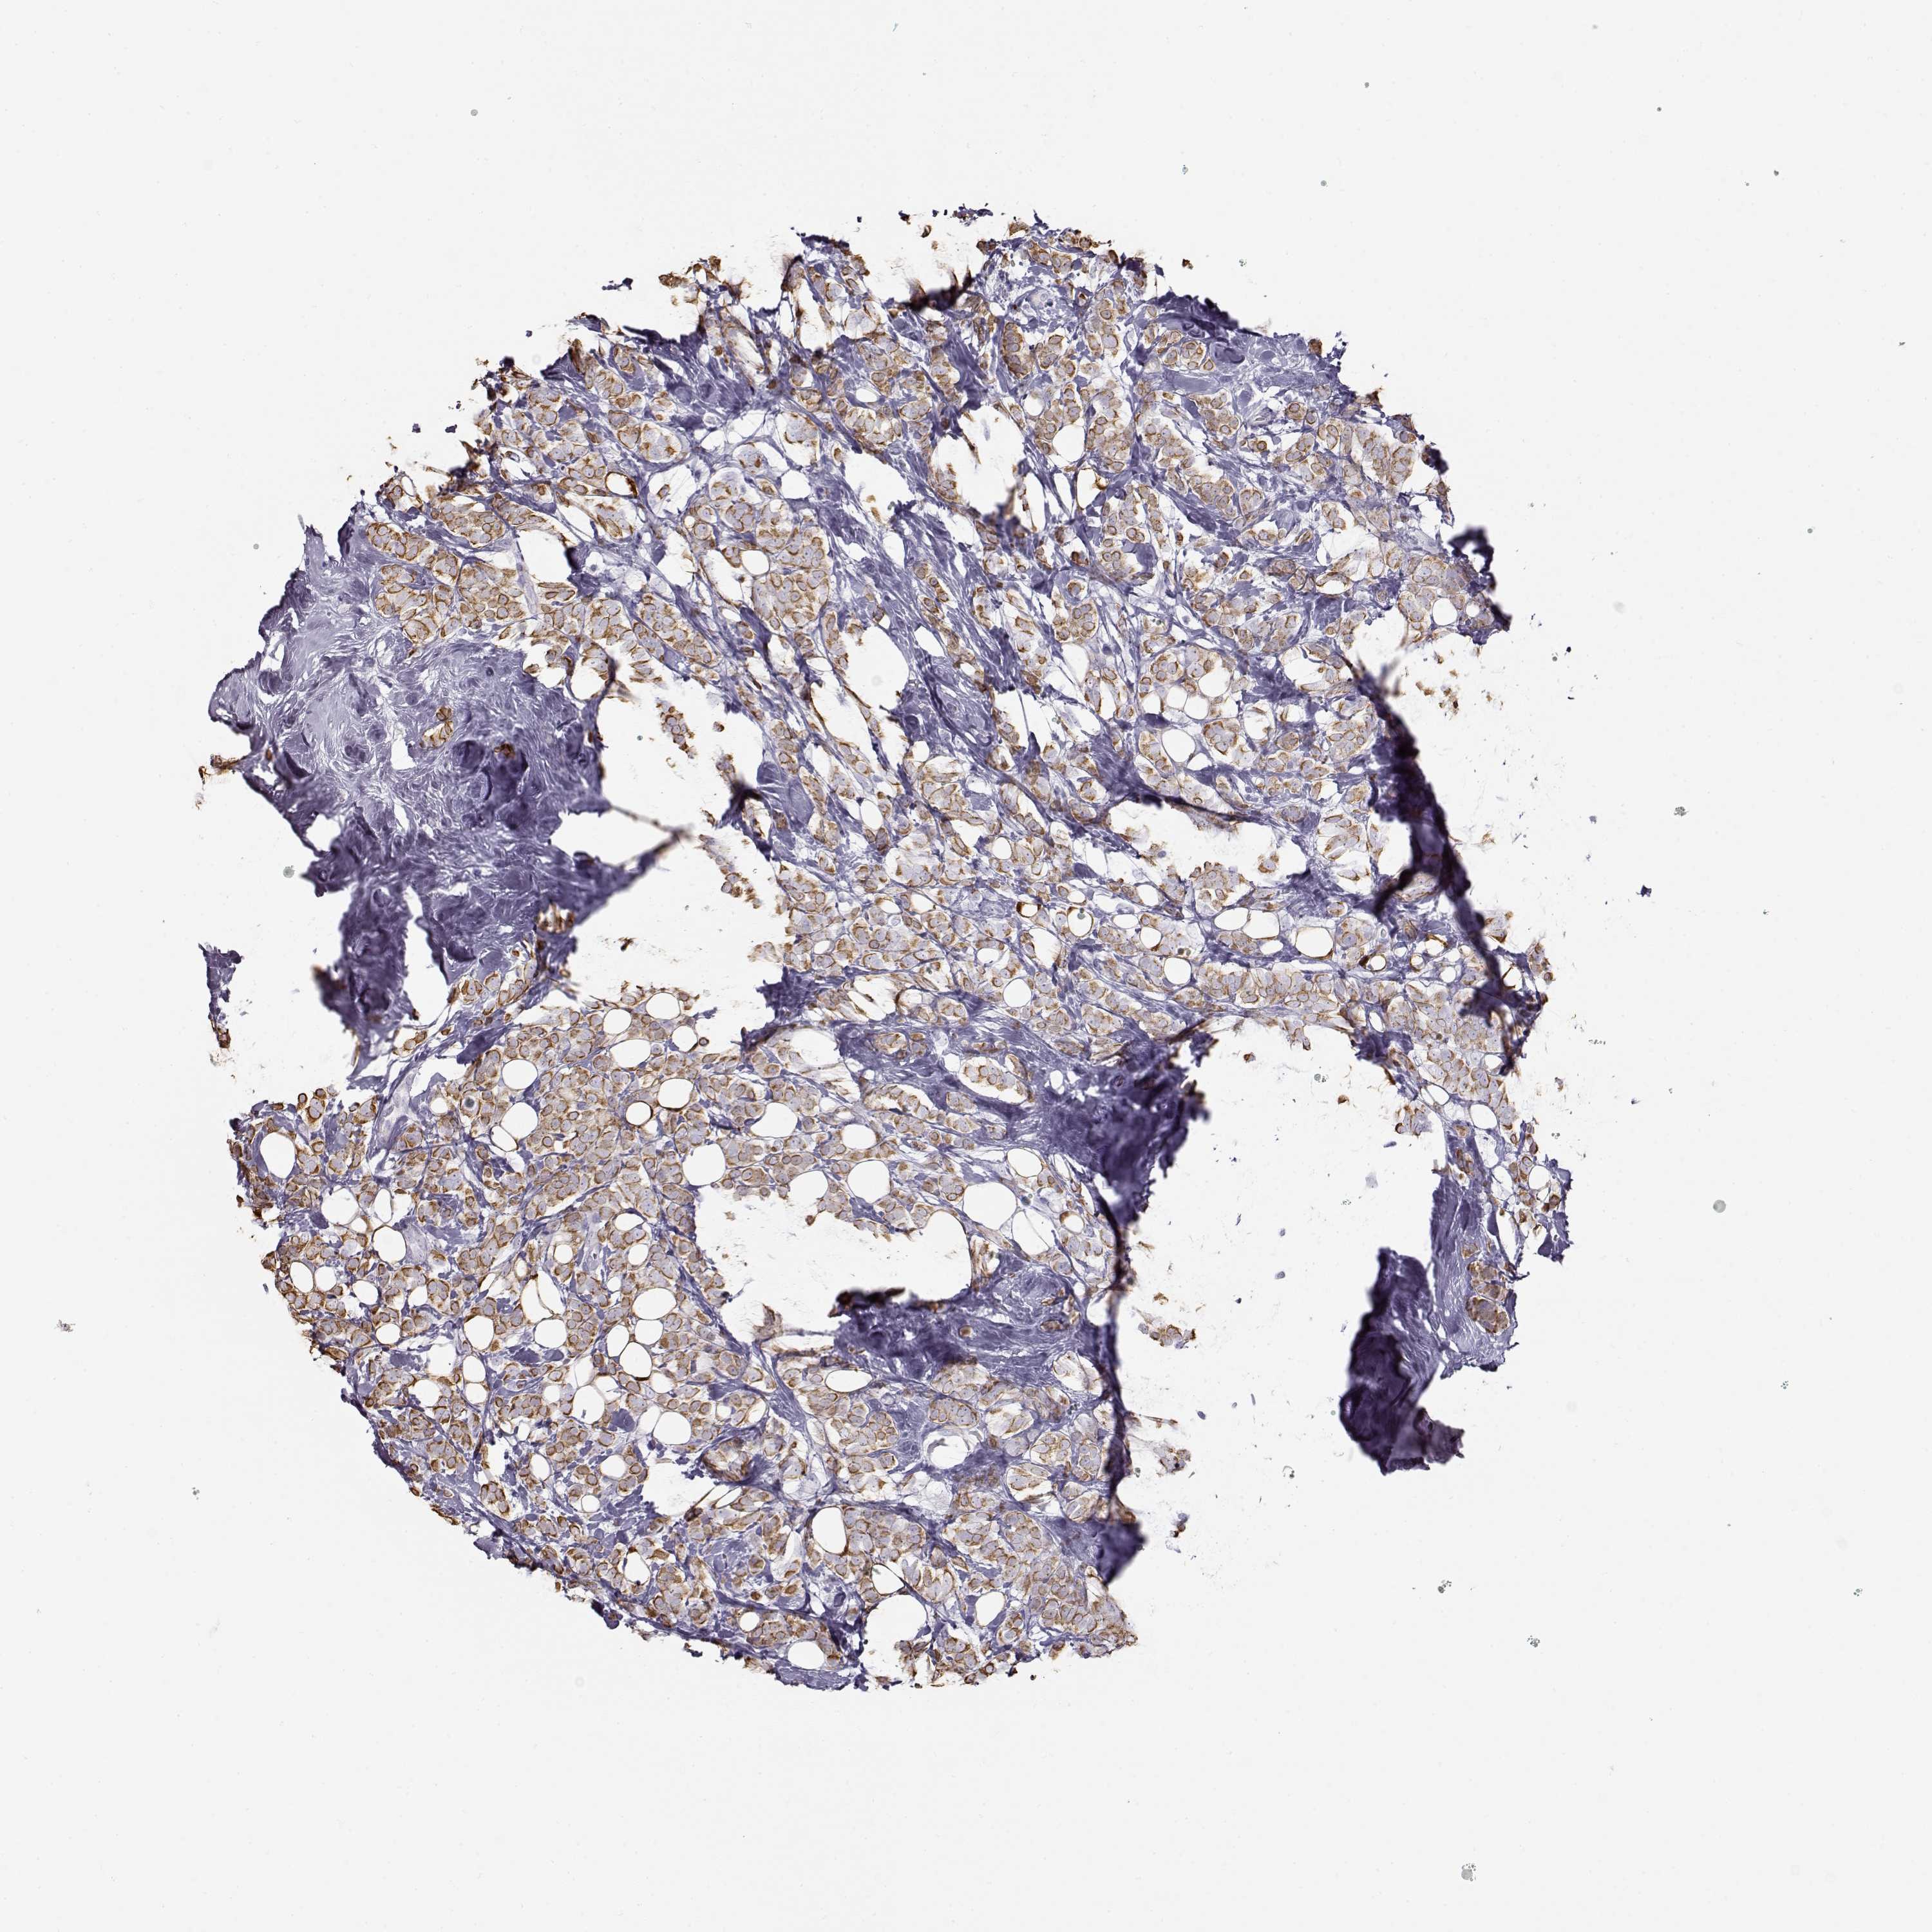

CANCER BREAST CANCER Show tissue menu

BRCA TCGA BRCA VALIDATION PROTEIN EXPRESSION